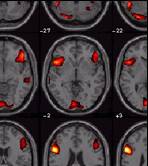

Visualisierung (SPM2)

• Render       Sections     Slices